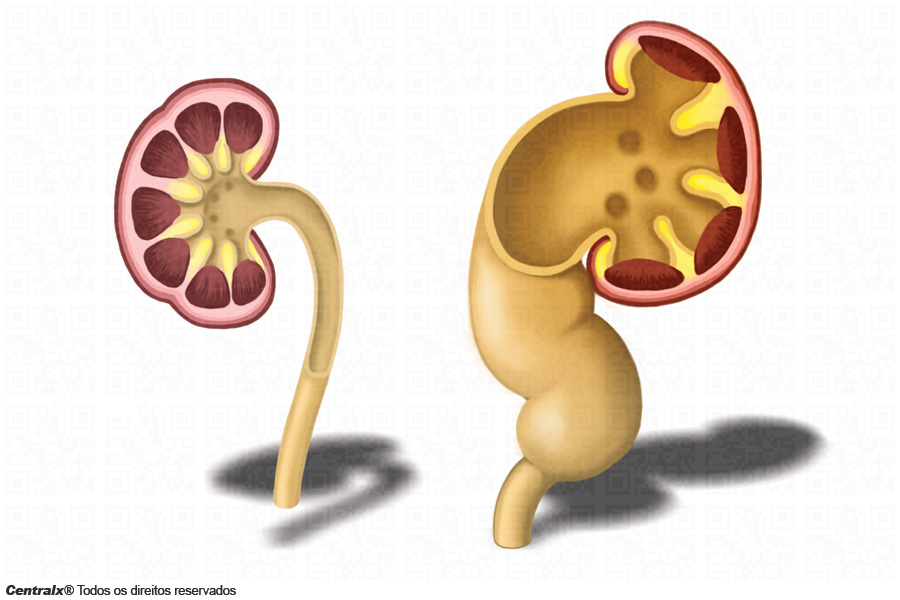

Рефлюксирующий мегауретер: Визуализация и медицинские изображения

Раздел: Фотопуть к знанию